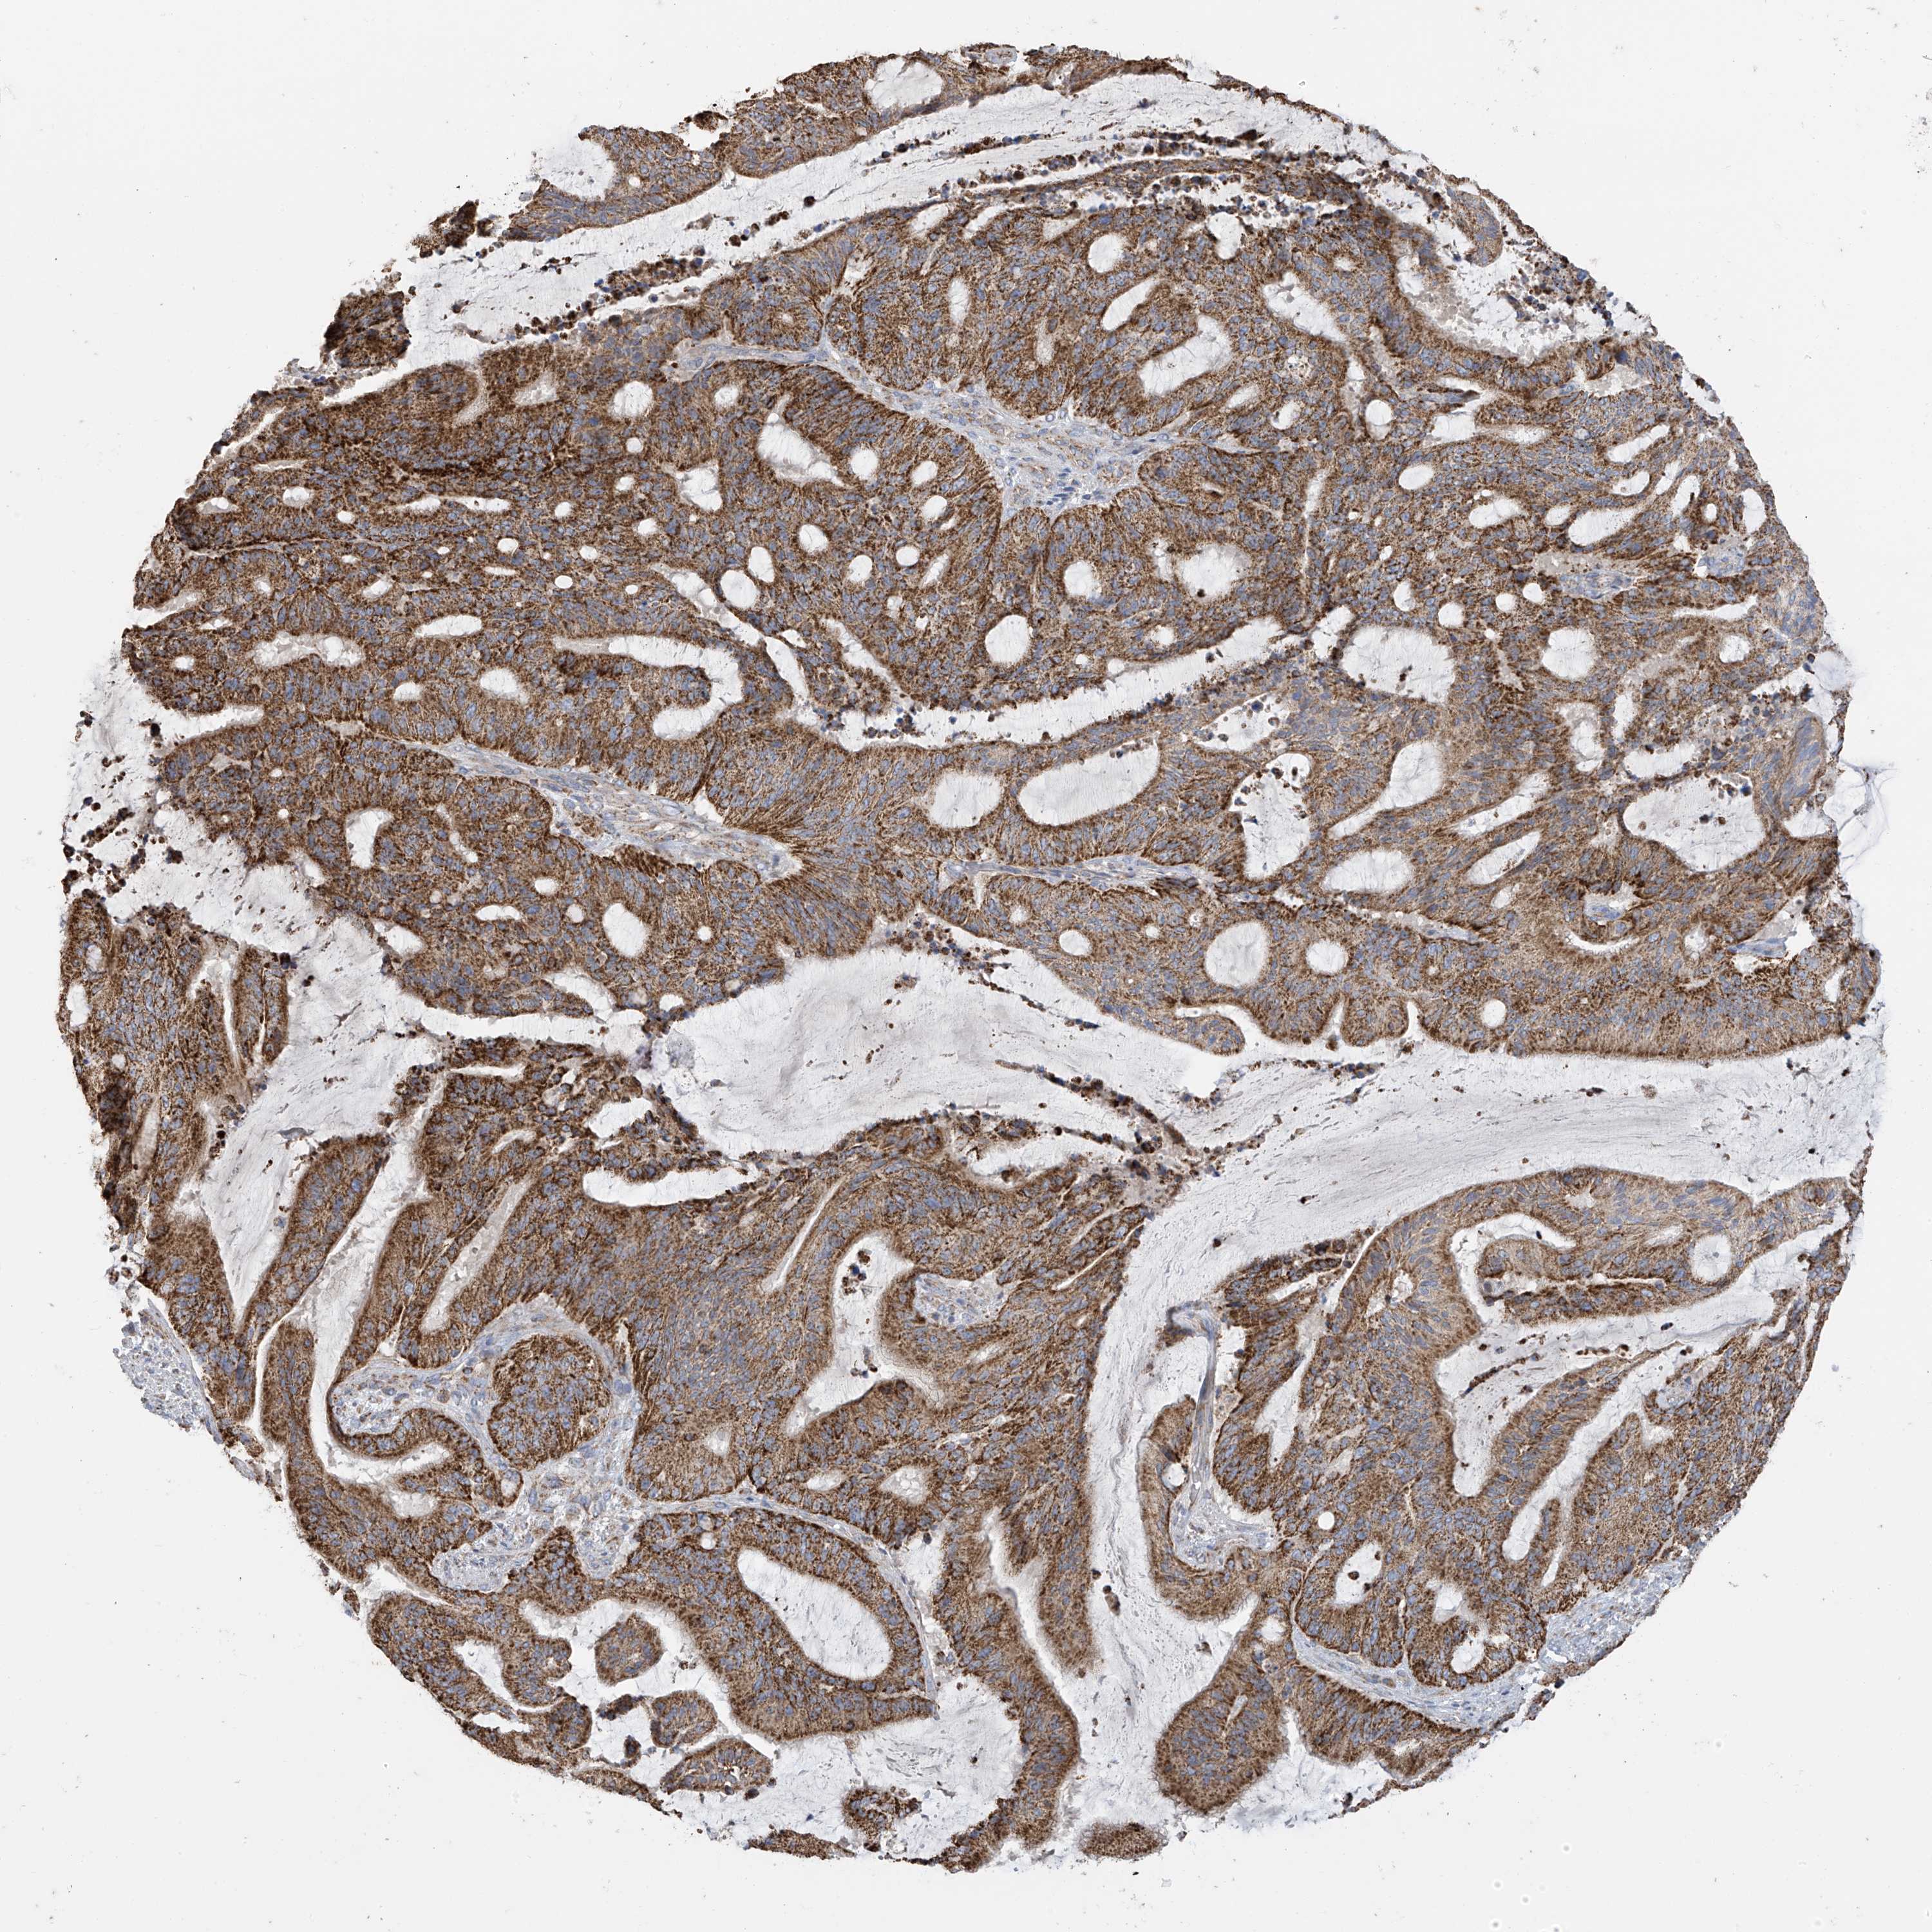

LIVER CANCER - Protein expressioni

A mouse-over function shows sample information and annotation data. Click on an image to view it in a full screen mode. Samples can be filtered based on level of antibody staining by selecting one or several of the following categories: high, medium, low and not detected. The assay and annotation is described here.

Note that samples used for immunohistochemistry by the Human Protein Atlas do not correspond to samples in the TCGA dataset.

Antibody stainingi

Antibody staining in the annotated cell types in the current human tissue is reported as not detected, low, medium, or high, based on conventional immunohistochemistry profiling in selected tissues. This score is based on the combination of the staining intensity and fraction of stained cells.

Each image is clickable and will lead to virtual microscopy that enables deeper exploration of all samples and also displays staining intensity scores, fraction scores and subcellular localization as well as patient and tissue information for each sample.

Antibody HPA034602

Antibody HPA034603

Antibody CAB033424

Staining

High

Medium

Low

Not detected

Intensity

Strong

Moderate

Weak

Negative

Quantity

>75%

75%-25%

<25%

None

Location

Nuclear

Cytoplasmic/membranous

Cytoplasmic/membranous,nuclear

Cholangiocarcinoma

Carcinoma, Hepatocellular, NOS